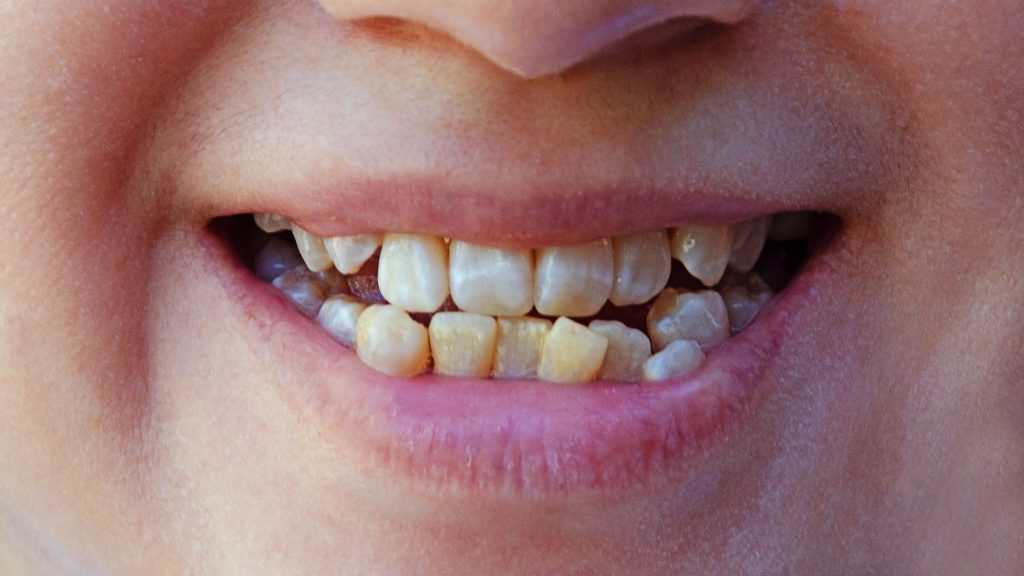

تزاحم الأسنان يعني إن الأسنان ما تلقى مساحة كافية عشان تترتب بشكل طبيعي داخل الفكين.

بعبارات بسيطة: الفك ضيّق أو تكون الأسنان كبيرة أو النمو غير منتظم — فتبدأ الأسنان تتزاحم، تصير ملتوية، أو يكون فيها اعوجاج، أو تراكب بين الأسنان الأمامية أو العلوية أو السفلية.

- وجود اعوجاج واضح في الأسنان الأمامية (العلوي أو السفلي)، بحيث تبدو الأسنان مائلة أو متراكبة.

- شكل الفكّ يبدو «ضيق» أو ما تلقى فيه مساحة كافية لظهور كل الأسنان — مما يؤدّي إلى تراكب أو دوران للأسنان.

- درجة بسيطة: تراكب بسيط أو مائل خفيف في الأسنان، ما يأثر كثير على الوظيفة لكن يفضل علاج مبكّر.

- درجة معتدلة: التراكب أو الاعوجاج تكون أوضح، تنظيف الأسنان يصير أصعب، وقد يظهر سوء إطباق بسيط أو ضغط من «ضرس العقل».

- درجة شديدة: الأسنان كثيرة متراكبة أو مائلة بشكل واضح، ممكن تكون المساحة جداً ضيقة أو يكون خلع ضروري أو تدخل موسّع للفكّ.